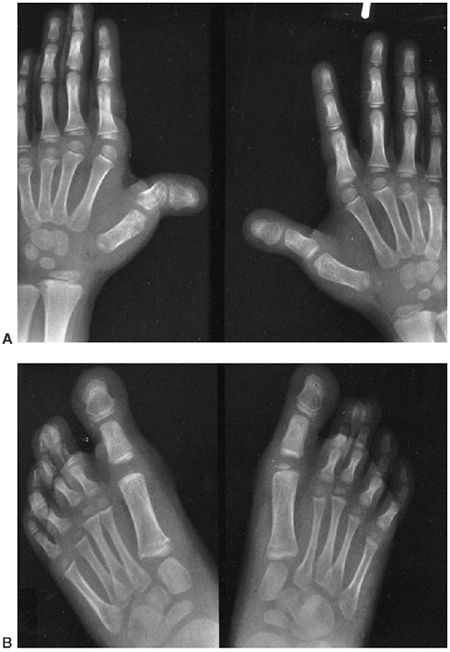

Arachnodactyly is defined, for purposes of radiographic readings, as an

increase in the ratio of length to width of the second to fifth

metacarpals (Fig. 9.2). The average ratio of

the lengths of the second to fifth metacarpals, divided by the widths

of the respective diaphyses, is greater than 8.8 in male patients and

greater than 9.4 in female patients with Marfan syndrome (21).

Figure 9.2 Hands showing arachnodactyly. Notice the long, thin metacarpals and phalanges.

|